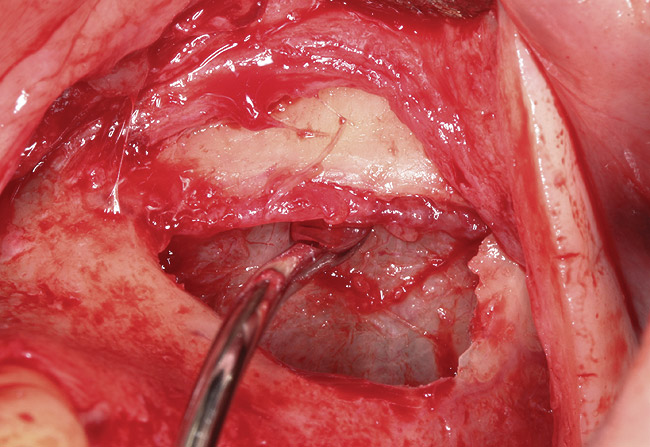

Fig 5. Window is covered with a collagen membrane, and the flap is sutured back into place.

Figure 5

Fig 6. Dissection and isolation of a major blood vessel from the sinus wall during surgery.

Figure 6